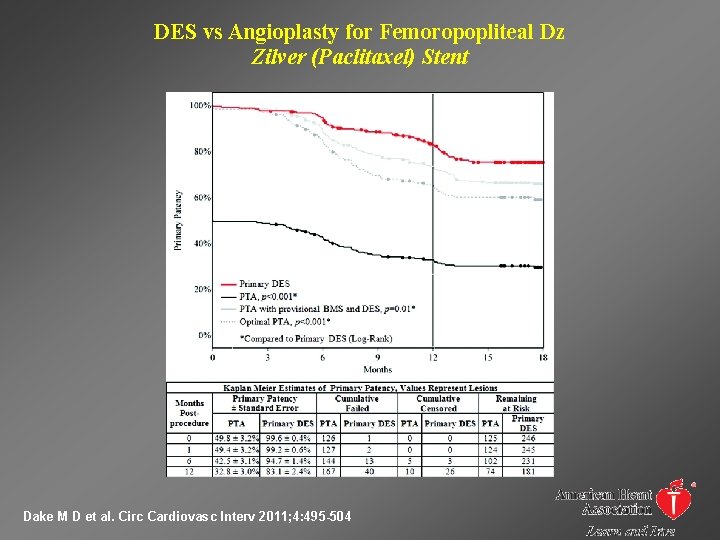

DES vs Angioplasty for Femoropopliteal Dz Zilver (Paclitaxel) Stent Dake M D et al. Circ Cardiovasc Interv 2011; 4: 495 -504